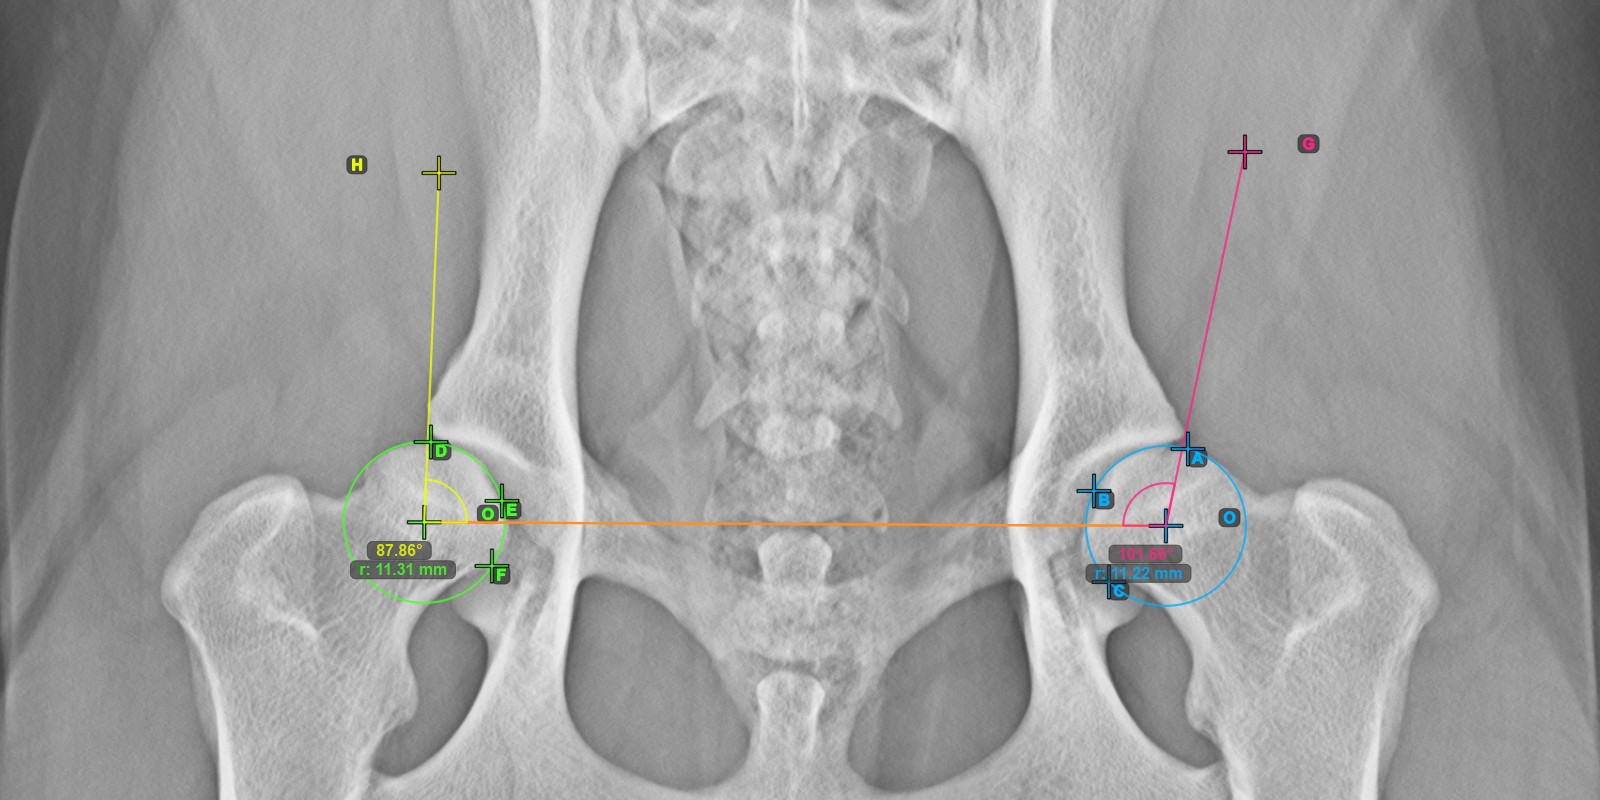

Calculate the right Norberg Angle measurement by marking a line on the effective edge of the right Acetabularis bone, completing the entire advanced measurement.

Mark a point near the right Caput Femoris and drag it along the effective edge of the right Acetabularis bone, forming the terminal side of the right Norberg Angle.

The drawn line must be a tangent to the effective edge of the right Acetabularis bone. The value and arc of the angle is automatically calculated.

The image below depicts the typical placement of the line and the calculated Norberg Angle measurement.